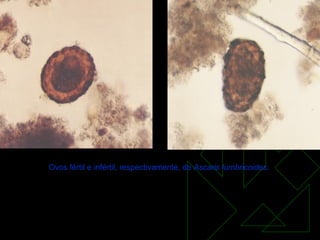

Ovos fértil e infértil, respectivamente, de  Ascaris lumbricoides .